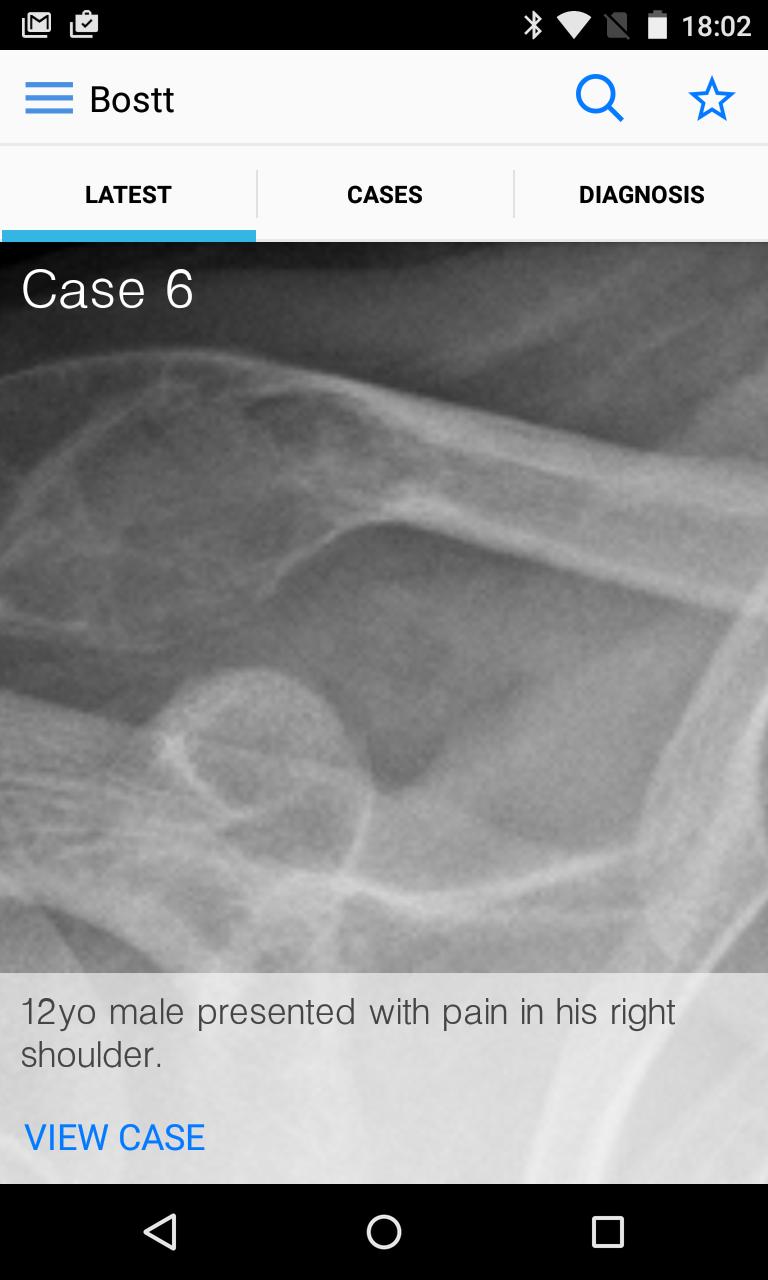

Estudios de caso de tumores de huesos y tejidos blandos. Una fuente de casos tumorales MSK/sarcoma.

BoSTT trae al usuario una experiencia real de casos frecuentes y raros, típicos y más inusuales de tumores de huesos y tejidos blandos. Cada caso tiene antecedentes clínicos, imágenes de radiología y patología de alta resolución, diagnóstico, tratamiento y puntos de aprendizaje.